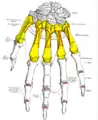

Vue palmaire des os de la main et des insertions musculaires (les métacarpiens en jaune).

Vue palmaire des os de la main et des insertions musculaires (les métacarpiens en jaune). Vue dorsale des os de la main et des insertions musculaires (les métacarpiens en jaune).